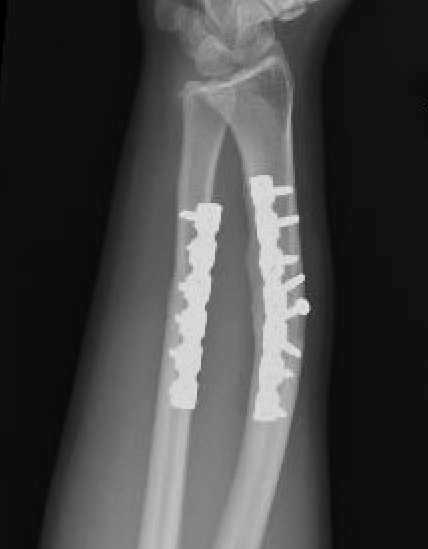

Radial malunion / Non anatomical ORIF of BBFF

Radial malunion after ORIF of BBFF

Etiology

Non operative management of BBFF

Non anatomical ORIF of BBFF

Bone loss radius

Radius short

Lengthening radius difficult

Ulna shortening

Radius angulated / rotated

Radial osteotomy

TFCC repair +/- TFCC reconstruction